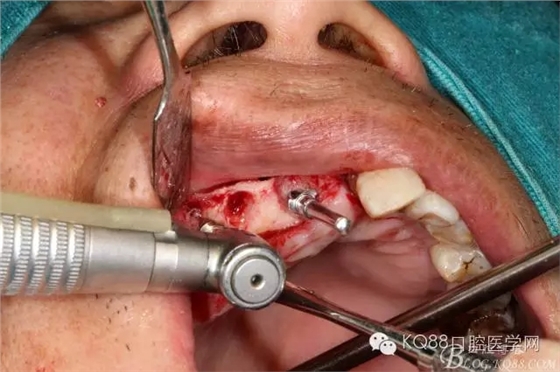

局部浸潤麻醉頰、腭側(cè)手術(shù)區(qū)域,拔除11、12、13.

設(shè)計斜橫切口,從牙槽嵴側(cè)翻開全厚瓣,搔刮牙槽窩內(nèi)肉芽組織,修整牙槽嵴頂。

小球鉆磨除埋伏牙頰側(cè)骨壁,牙挺挺出埋伏牙,清理拔牙窩

金剛砂球鉆制備橢圓形骨窗,遠(yuǎn)中邊緣延伸到上頜結(jié)節(jié),取下骨島,骨角和尖銳的邊緣打磨圓鈍,暴露上頜竇黏膜,分離提升上頜竇黏膜。

定位桿定位,擴孔,備洞,bio-oss骨粉和CGF混合后充填竇腔

植入植體,骨島覆蓋上頜骨側(cè)壁骨窗

bio-guide屏障膜覆蓋側(cè)壁骨窗,牙槽嵴頂缺損部位植骨,嚴(yán)密縫合。